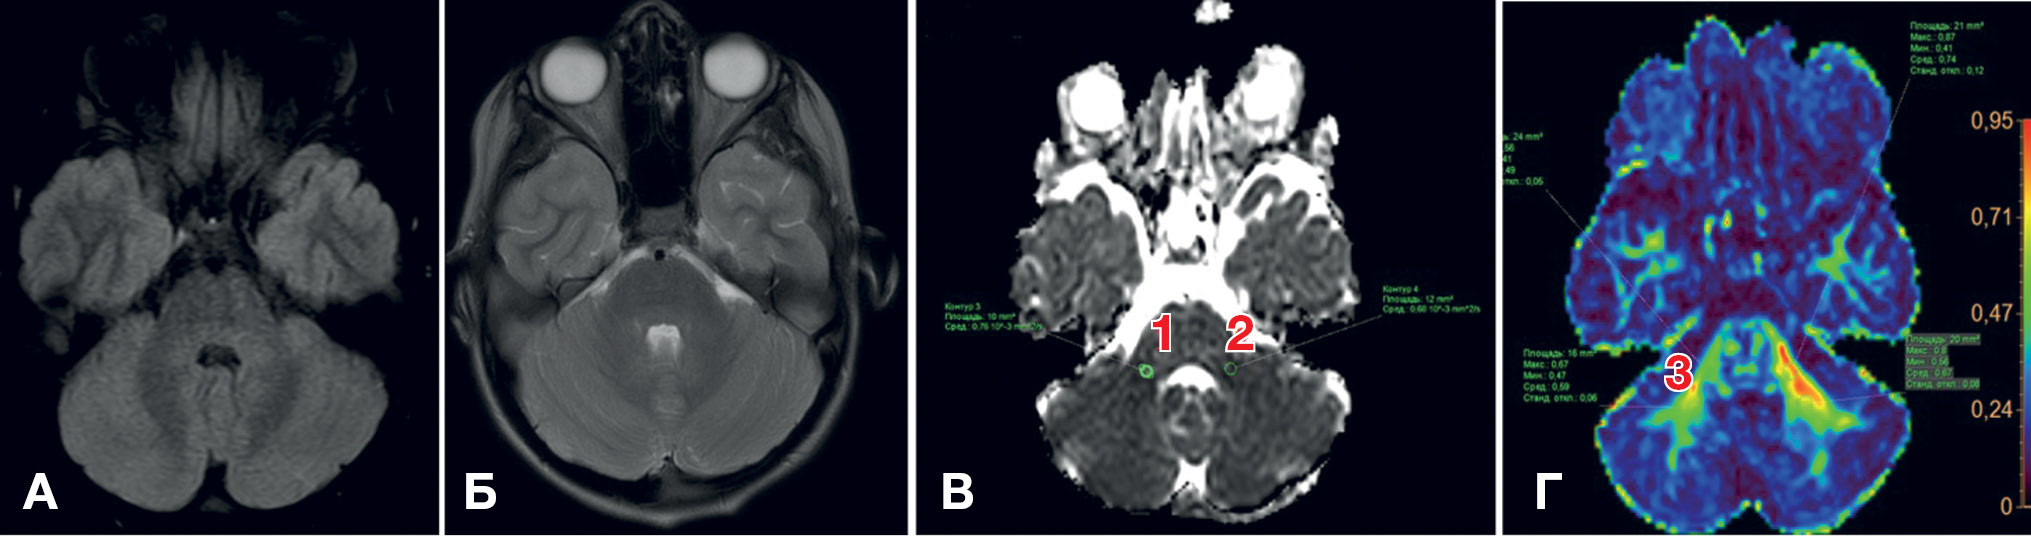

Пример изменений на МРТ у детей с вирусными энцефалитами, выявляемых с помощью фракционной анизотропии, представлен на рис. 2.

Рис. 2. МРТ головного мозга пациентки Х., 4 года: энцефалит цитомегаловирусной этиологии, острый период заболевания

Примечание. Снижение значений фракционной анизотропии при выполнении диффузионно-тензорной методики (DTI) в очагах косвенно свидетельствует о наличии в них цитотоксического отека; отмечается также сохранение целостности трактов (собственные данные).

Пример изменений, не выявленных методом структурной МРТ, но обнаруженных с помощью мультипараметрической МРТ у ребенка с вирусным энцефалитом, представлен на рис. 4.

Рис. 4. МРТ головного мозга пациента М., 10 лет: энцефалит цитомегаловирусной этиологии

Примечание. А, Б — убедительные изменения на Т2-, FLAIR- и DWI-режимах отсутствуют. В, Г — снижение фракционной анизотропии в правой ножке (1) и полушарии мозжечка (2, 3) в сравнении с контралатеральной стороной (косвенные признаки снижения нейрональной плотности), сохранение целостности трактов (собственные данные).